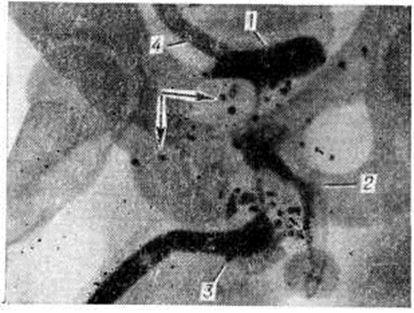

Мочеполовые свищиМочеполовые свищи — патологические сообщения между органами мочевой и половой систем. Различают врождённые и приобретённые Мочеполовые свищи. Врождённые Мочеполовые свищи чаще наблюдаются у мужчин. Врождённый уретропростаторектальный свищ обычно сочетается с anus imperforatus, и его диагностируют после рассечения anus. К врождённым свищам относят эктопию одного или двух устьев мочеточников во влагалище у женщин и в предстательную часть уретры, семенные пузырьки и семявыносящий проток у мужчин. Приобретённые Мочеполовые свищи могут возникать у женщин в результате повреждений во время патологический родов, акушерских и гинекологическое операций, при медицинских и криминальных абортах, насильственного coitus при атрезии влагалища. Мочеполовые свищи образуются также после огнестрельных ранений и травм промежности с переломом костей таза, при гнойно-воспалительных заболеваниях, при прогрессирующем росте опухолей малого таза с вовлечением в процесс мочевых н половых органов, после лучевой терапии. У мужчин причиной множественных свищей, открывающихся на мошонке, половом члене и промежности, может быть туберкулёз и актиномикоз. Различают наружные и внутренние Мочеполовые свищи К наружным относят уретро-простато-промежностный, уретро-мошоночный и другие свищи, у которых одно из отверстий открывается на коже, к внутренним — везиковагинальные, уретеровезикальные, овариовезикальные, сальпинговезикальные, параметровезикальные, уретеровагинальные, уретровагинальные, уретровезикальные, уретропростаторектальные, сложные и комбинированные. Иногда внутренний Мочеполовые свищи может сочетаться с наружным искусственным надлобковым мочепузырным свищом, созданным для дренирования мочевого пузыря. Везико-вагинальные свищи встречаются чаще других и возникают обычно после продолжительных травматичных родов при узком тазе. Ранение мочевого пузыря при кесаревом сечении, экстирпации матки, плодоразрушающих операциях и операциях, предпринимаемых по поводу кист передней стенки влагалища, парауретральных кист и дивертикулов уретры, может привести к возникновению везико-вагинальных, уретровагинальных и уретровезиковагииальных свищей. Наружные Мочеполовые свищи легко выявить при осмотре, особенно если предварительно ввести в мочеиспускательный канал раствор индигокармина. Диагноз уточняют уретрои фистулографией. Лечение наружных Мочеполовые свищи, как правило, оперативное: иссекают свищевой ход и производят пластику мочеиспускательного канала с временным отведением мочи по цистостомическому дренажу. Везико вагинальные свищи. Симптоматика везико-вагинальных свищей зависит от их локализации и величины. При значительных дефектах дна и стенки мочевого пузыря у больных моча целиком выделяется через влагалище. При небольших, особенно точечных свищах, наряду с подтеканием мочи сохраняется адекватное самостоятельное мочеиспускание. Расположение свищевого отверстия ниже мочепузырного треугольника усиливает подтекание мочи, если больная находится в вертикальном положении, а при локализации его в области дна выделение мочи из влагалища возникает преимущественно в горизонтальном положении больной. Диагноз везико-вагинальных свищей основывается на данных влагалищного исследования, при котором легко обнаруживают большие фистулы. При исследовании влагалища с помощью зеркал определяют состояние шейки матки, стенки влагалища и влагалищное отверстие свища, чему способствует выделение мочи или предварительное введение в мочевой пузырь окрашенной жидкости. Цистоскопия (смотри полный свод знаний) и хромоцистоскопия (смотри полный свод знаний) позволяют уточнить местоположение пузырного отверстия свища, наличие сопутствующего цистита (смотри полный свод знаний) или камней, взаимоотношение свища с устьями мочеточников и функцию верхних мочевых путей. При точечных и небольших свищах цистоскопия легко осуществима, особенно при использовании постоянного тока жидкости, вводимой в мочевой пузырь. Большие свищи требуют предварительного тампонирования влагалища надувным баллоном или марлевым тампоном, смоченным жидким вазелином. Исследование влагалища с помощью зеркал и цистоскопию можно сочетать с зондированием свища. Рентгенодиагностика везико-вагинальных свищей базируется на цистографии (смотри полный свод знаний) и вагинографии (смотри полный свод знаний Кольпография), которая подтверждает наличие свища и даёт представление о состоянии и ёмкости мочевого пузыря и влагалища (рисунок 1). |

Рис. 1. | ||